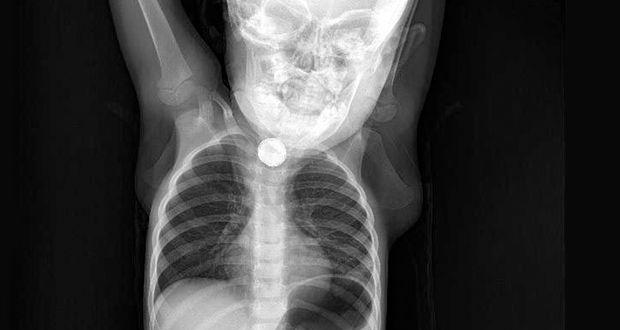

Batman’da Sevim ve İbrahim Ramazanoğlu çiftinin kusma ve ishal şikayetiyle hastaneye götürdüğü kızları Berfin’in (1,5) yassı pili yuttuğu belirlendi. Yemek borusunda ciddi yanıklar meydana gelen Berfin’in boğazının alt kısmındaki pil, operasyonla alındı.

DHA’nın haberine göre; Batman’da yaşayan Ramazanoğlu çifti, bulantı, iştahsızlık ve ishal beliren kızları Berfin’i Batman Devlet Hastanesi’ne götürdü. Doktorun muayene ettiği Berfin’in yemek borusunda cisim tespit edildi. Bunun üzerine Berfin, Elazığ Fırat Üniversitesi Hastanesi’ne sevk edildi. Burada yapılan kontrolde yassı pil yuttuğu tespit edilen Berfin, ameliyata alındı. Küçük kızın boğazının alt kısmındaki pil, başarılı operasyonla çıkarıldı. Ramazanoğlu çifti ise kızlarının, yaklaşık 3 ay önce yerde oynarken, bir cisim yuttuğunu hatırlayınca, pil yutmuş olabileceğini söyledi.

Operasyonu gerçekleştiren Tıp Fakültesi Çocuk Gastroenteroloji, Hepatoloji ve Beslenme Bilim Dalı Başkanı Prof. Dr. Yaşar Doğan, “Tanı amaçlı yaptığımız endoskopi neticesinde, Berfin´in, yassı bir pil yuttuğunu belirledik. Pili çıkardıktan sonra uzun süre orada kalmasından dolayı yemek borusunda ciddi yanıklar meydana gelmişti. Hatta bu yanıklar nerdeyse nefes borusuyla birleşecek şekilde bir oluşuma gidecekti. Hastamız şu an sağlığına kavuştu. Kliniğimizde şu an oral beslenmeye geçildi. Yarın taburcu etmeyi düşünüyoruz. Yine takiplerimiz devam edecek” dedi.